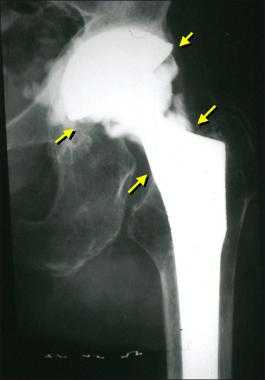

Дислокация бедренного компонента на рентгене.

Стрелками указаны зоны инфекционного воспаления, именно так они выглядят на рентгене.